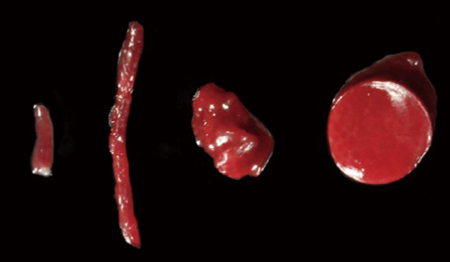

생검의 종류로는 중심부 바늘 생검(Core biopsy), 복강경을 이용한 생검(Laparoscopic biopsy), 그리고 개복술을 이용한 생검(Surgical biopsy)이 있습니다.

각각의 생검방법은 장단점이 존재하지만, 개복술이 진행되는 경우에는 수술생검을 진행하면 되며, Wedge biopsy를 사용했으나 최근에는 punch biopsy device를 이용하고 있습니다.

Core biopsy와 Laparoscopic biopsy는 적용은 병원내 구비되어 있는 장비에 따라 고민이 될 수 있습니다.Laparoscopic biopsy는 기본적으로 복강경과 다양한 forcep이 필요하며, 이런 장비들을 다뤄야 할 테크닉이 필요합니다. Core biopsy의 경우 초음파 장비와 biopsy device만 있으면 되며, 최소한의 교육으로도 가능할 수 있습니다.

물론 생검 결과는 생검을 실시하는 술자의 숙련도에 따라 Sample quality가 달라지기 때문에 결과도 변화할 수 있으므로 숙련된 수의사가 실시하는 것이 권장됩니다.

Core biopsy는 병원에서 비교적 쉽게 진행할 수 있는 방법입니다. 생검이 지시되는 환자가 선택되었다면 다음과 같이 평가하여야 합니다.

Core biopsy needle 14 G needle(대형견), 16 Gneedle (소형견이나 고양이)